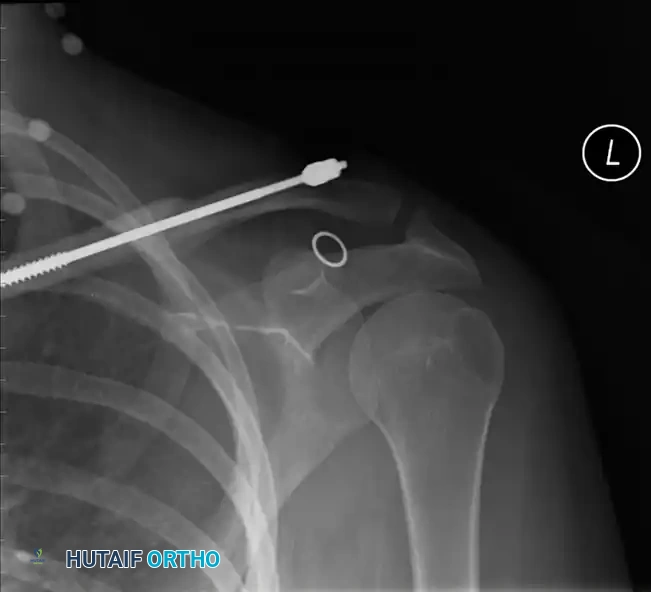

Fig. 54-3A: Preoperative radiograph demonstrating a severely displaced floating shoulder variant.

Image

Fig. 54-3D: Postoperative radiograph showing restoration of the SSSC via plate osteosynthesis of both the clavicle and the lateral border of the scapula.